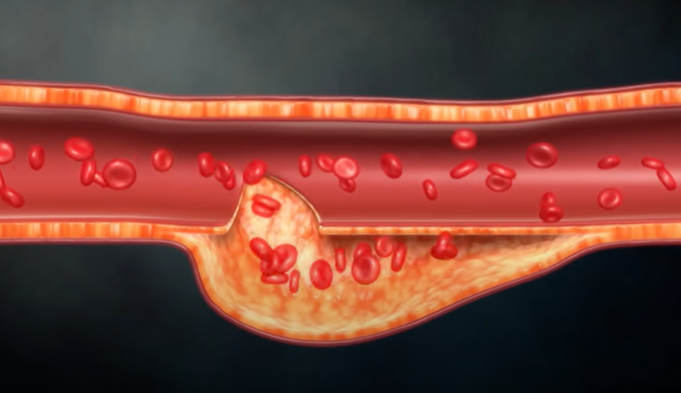

혈관 기형이 있다거나 혈전이 생겨서 혈관이 부풀어 오른다든지, 특히 정맥에 혈전이 생기면 두통이 심하게 나타날 수 있고, 또 하나는 머리 안쪽에 염증이 생기는 경우로서 뇌막염, 수막염, 뇌염, 결핵성 내막염이 있다. 또는 뇌압이 너무 올라가거나 떨어지면 심한 두통이 올 수 있다. 뇌압을 올리는 것은 뇌종양이 있다. 뇌에는 물이 있어 물을 만들어 내는 것이 너무 과다하거나 하루 3번 순환해야 하는데 물의 순환 과정이 막혀 물이 빠져나가지 못하는 경우에는 수두증이 생긴다.